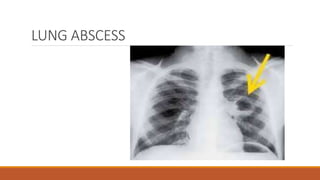

Lung abscess